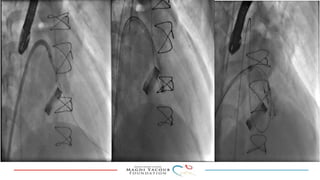

This document provides an overview of percutaneous prosthetic valve leakage (PVL) closure, including indications, approaches, techniques, and closure devices. It discusses that over 210,000 prosthetic valve surgeries are performed each year, with PVL occurring in some cases. While surgical closure has a high mortality rate, percutaneous closure has a procedural success rate of 86% and less complications. Indications for closure include symptomatic heart failure, hemolysis, rocking prosthesis, or leaks over 30% of the sewing ring. Techniques discussed include retrograde and transapical approaches using devices like the Amplatzer and Occlutech plugs. A team approach and techniques like sequential deployment are emphasized for